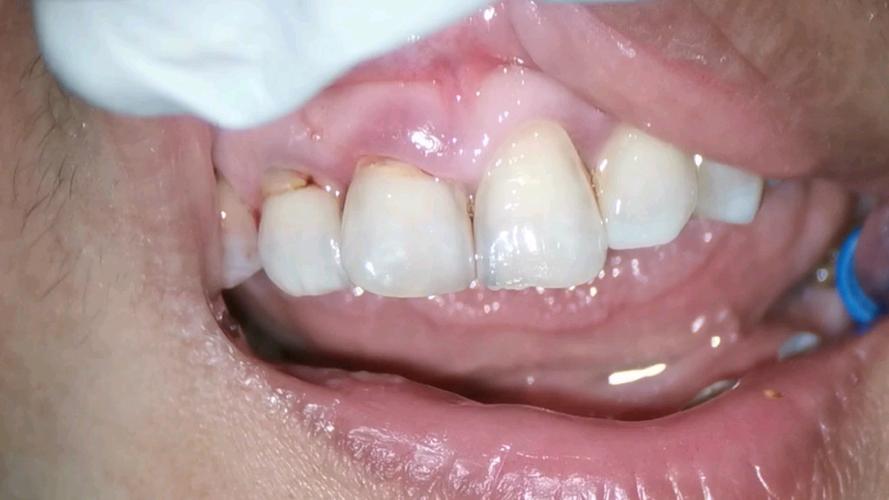

牙根裸露的本质是牙龈组织的退缩,使原本被牙龈包裹的牙根表面暴露出来,牙齿表面覆盖着一层牙釉质,是最坚硬的组织,但牙根表面覆盖的是牙骨质,下方连接着敏感的牙本质,一旦暴露,外界刺激(冷、热、酸、甜)容易通过牙本质小管传递至牙髓,引发敏感症状,在矫正牙齿时,牙齿需要在牙槽骨内移动,牙槽骨会随之发生改建——受压侧骨吸收,牵引侧骨增生,若矫正力度过大、移动速度过快,或患者自身牙槽骨条件较差(如骨量不足、骨质疏松),可能导致牙槽骨过度吸收,进而牵连牙龈组织,使其失去支撑而萎缩,形成牙根裸露。

牙根裸露的影响不容忽视,首先是牙齿敏感,患者可能在进食冷饮、甜食或刷牙时感到酸痛,影响生活质量;其次是美观问题,暴露的牙根呈淡黄色,与牙冠颜色差异明显,尤其在前牙区会影响笑容;长期未处理,牙根持续暴露可能导致牙根面龋坏(牙根蛀牙),严重时甚至引发牙齿松动、脱落,威胁口腔健康。